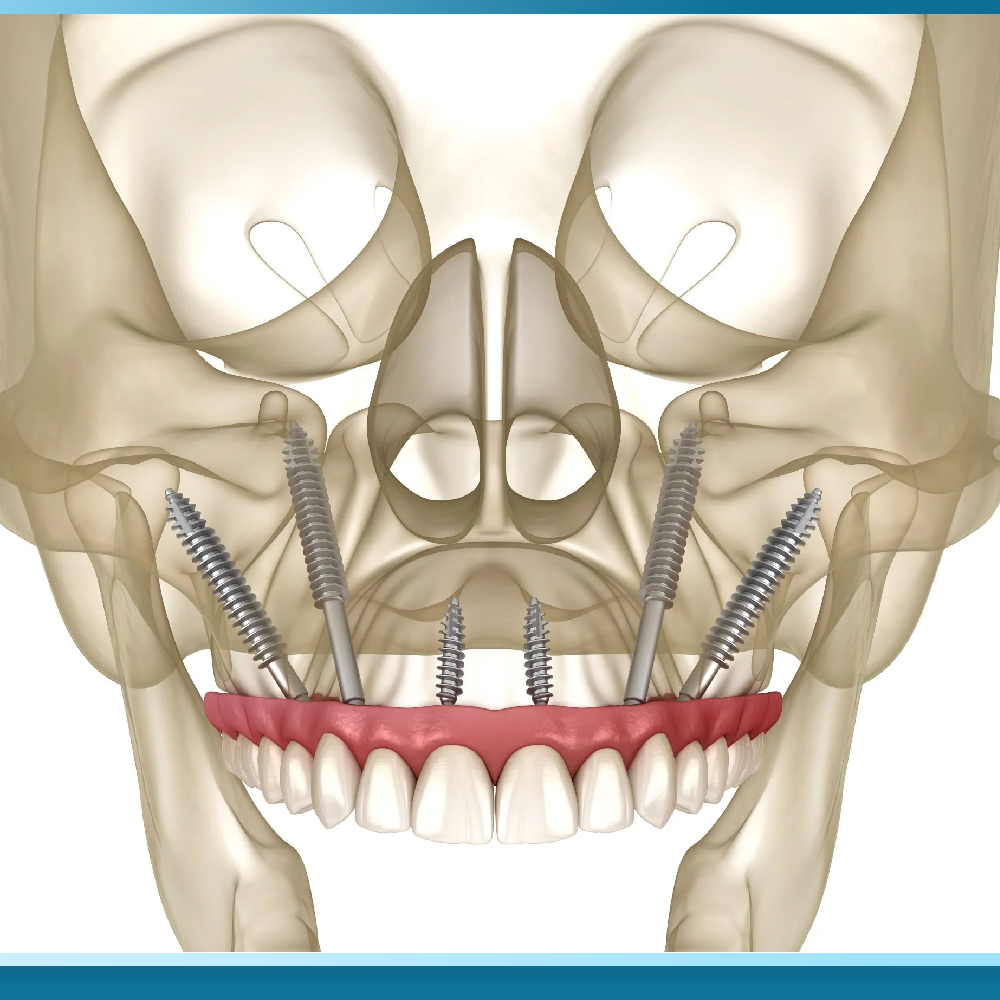

Kỹ thuật này sử dụng các trụ Implant có thiết kế đặc biệt với chiều dài vượt trội, thường dao động từ 30mm đến 50mm, gấp 3 đến 4 lần so với các loại trụ thông thường để xuyên qua vùng xương hàm đã tiêu biến và neo giữ trực tiếp vào xương gò má.

Xương gò má có đặc tính sinh học rất quan trọng là mật độ xương cực kỳ cứng chắc và hầu như không bị tiêu biến theo thời gian, ngay cả khi bệnh nhân bị mất răng lâu năm hoặc mắc các bệnh lý về xương hàm. Khi kết hợp với phác đồ All on 6, bác sĩ sẽ cấy ghép từ 2 đến 4 trụ Implant gò má ở vùng răng sau, kết hợp với các trụ Implant thông thường ở vùng răng cửa phía trước để tạo thành một hệ thống nâng đỡ vững chãi.

Sự kết hợp này cho phép phân bổ lực nhai đều khắp cung hàm, đảm bảo tính bền vững và an toàn cho hàm phục hình sứ bên trên. Phương pháp này đòi hỏi sự tính toán chuẩn xác về giải phẫu học để tránh tác động đến các cấu trúc nhạy cảm như xoang hàm hay hốc mắt.